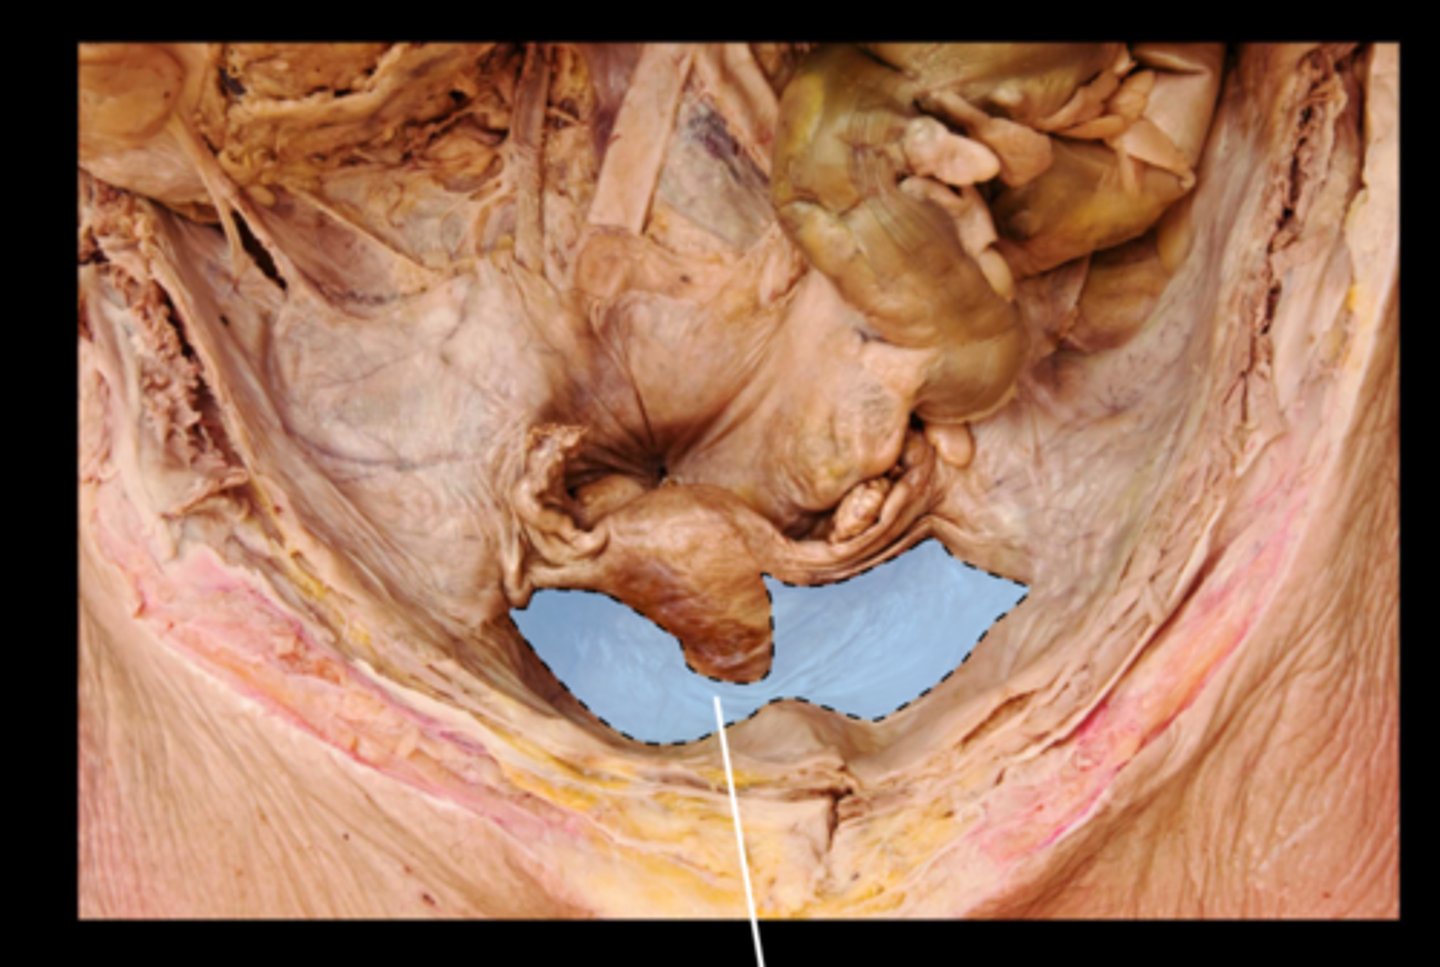

Rectum